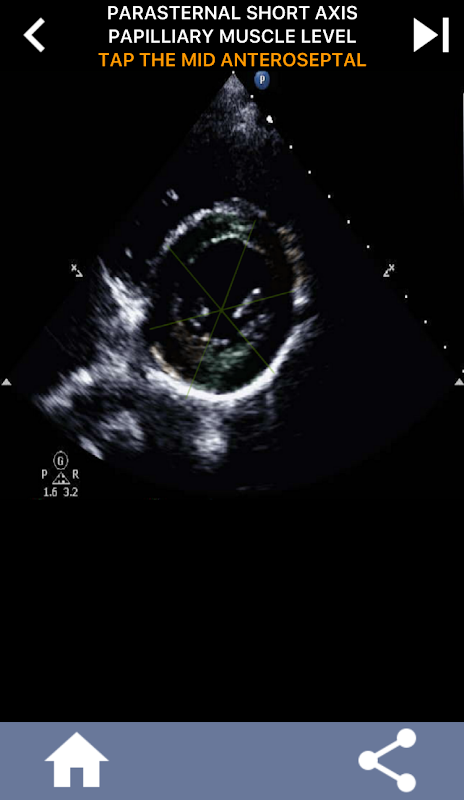

Визуальный подход к изучению сегментов сердца AHA на основе викторины: эхокардиография

Понимание сегментов сердца AHA (Американской кардиологической ассоциации) имеет первостепенное значение для кардиологического УЗИ, чтобы эффективно общаться с кардиологом, который пишет отчет. Зная конкретные анатомические области и соответствующие им сегменты, сонографист может точно описать и сообщить о любых аномалиях или результатах, обеспечивая четкое и краткое общение между обоими специалистами.

Это понимание становится особенно важным, когда кардиолог стремится установить точное местоположение проблемы или когда дежурный врач выявляет проблему в определенной области, побуждая сонографа точно отображать соответствующий сегмент, например, среднюю нижнюю стенку. Таким образом, всестороннее понимание сегментов сердца AHA является важным набором навыков.

Это приложение проверит ваши знания, используя реальные эхо-изображения, которые я часто считаю лучшим методом обучения.